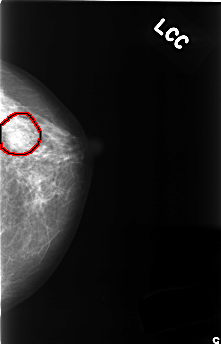

C_0385_1.LEFT_CC

LEFT_CC LINES 4464 PIXELS_PER_LINE 2872 BITS_PER_PIXEL 12 RESOLUTION 50 OVERLAY

FILE: C_0385_1.LEFT_CC.OVERLAY

TOTAL_ABNORMALITIES 1

ABNORMALITY 1

LESION_TYPE MASS SHAPE OVAL MARGINS OBSCURED

ASSESSMENT 4

SUBTLETY 4

PATHOLOGY BENIGN

TOTAL_OUTLINES 1

BOUNDARY